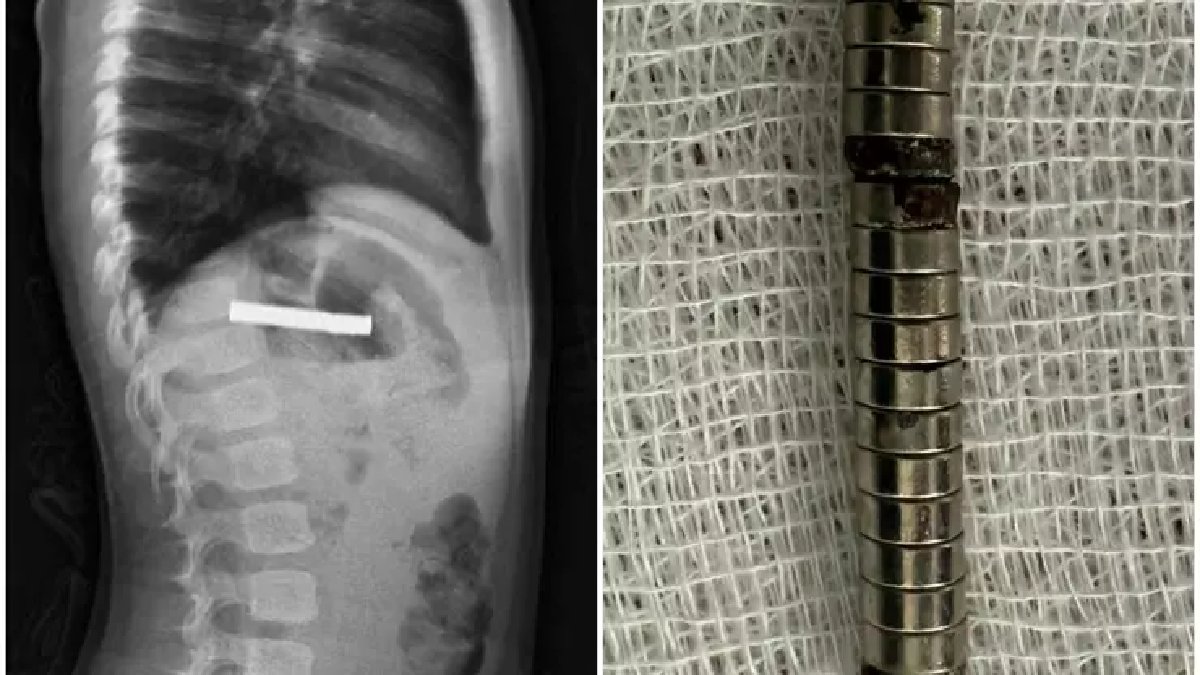

Erzurum'dan sevk edilen küçük çocuğun tedavisi, Fırat Üniversitesi Tıp Fakültesi Çocuk Gastroenteroloji, Hepatoloji ve Beslenme Bilim Dalı Başkanı Prof. Dr. Yaşar Doğan ve ekibi tarafından üstlenildi. Çocuğun durumunun ciddiyeti üzerine hızla harekete geçen ekip, endoskopik yöntemle müdahale kararı aldı. Başarılı geçen operasyon sonucunda, çocuğun yemek borusuna yapışmış halde bulunan 19 mıknatıs tek tek çıkarıldı.

MIKNATISLAR ZEDELENMEYE YOL AÇTI

Mıknatısların bir süre çocuğun sindirim sisteminde kalması, bazı hasarlara neden oldu. Hastaneden yapılan açıklamada, yutulan mıknatısların mide girişinde ve yemek borusu duvarında zedelenmelere yol açtığı belirtildi. Zamanında ve doğru müdahale sayesinde çocuk gerekli tedavisini aldıktan sonra sağlığına kavuşarak taburcu edildi. Uzmanlar, ebeveynleri küçük çocukların kolayca yutabileceği küçük ve tehlikeli oyuncak parçalarına karşı bir kez daha uyardı.